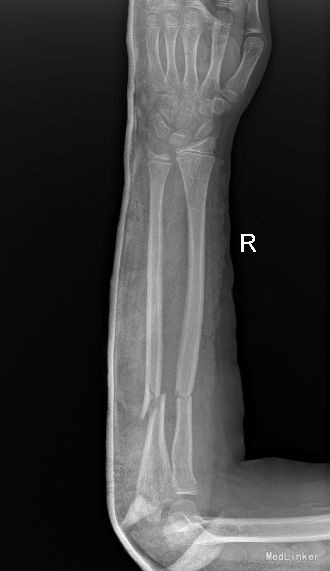

主 诉:摔倒致右前臂疼痛、畸形、活动受限14天。 现病史:14天前,患者在玩耍时摔倒,右前臂先触地,即感右前臂疼痛、畸形、活动受限,受伤当时无头晕头疼,无恶心呕吐等不适。被家人送入我院,行右前臂正侧位X线检查示“右尺桡骨骨折”,手法复位并石膏托固定后复查示“骨折断端对位对线尚可”,嘱患者定期随诊。今患者来我院复查,行右前臂正侧位片检查示“骨折断端对位对线欠佳,桡骨远折端向背侧成角”,患者家属要求住院手术治疗,门诊经检查后以“右尺桡骨骨折”位诊断收入我科。发病以来,神志清楚,精神尚可,无恶寒发热,饮食、大小便正常,睡眠可,体重无明显变化。

专科检查:步入病房。右前臂石膏托固定,去除石膏托后右前臂未见明显肿胀,中段压痛阳性,纵向叩击痛阳性,可触及骨擦感,因前臂疼痛致右肘、腕关节活动受限,肘后三角正常,腕关节、肘关节压痛阴性,右前臂痛触觉较左侧未见明显异常,右侧桡动脉搏动可扪及,末梢血液循环可。

西医诊断:右尺桡骨骨折 治疗:全麻下行“右尺骨骨折切复内固定术”